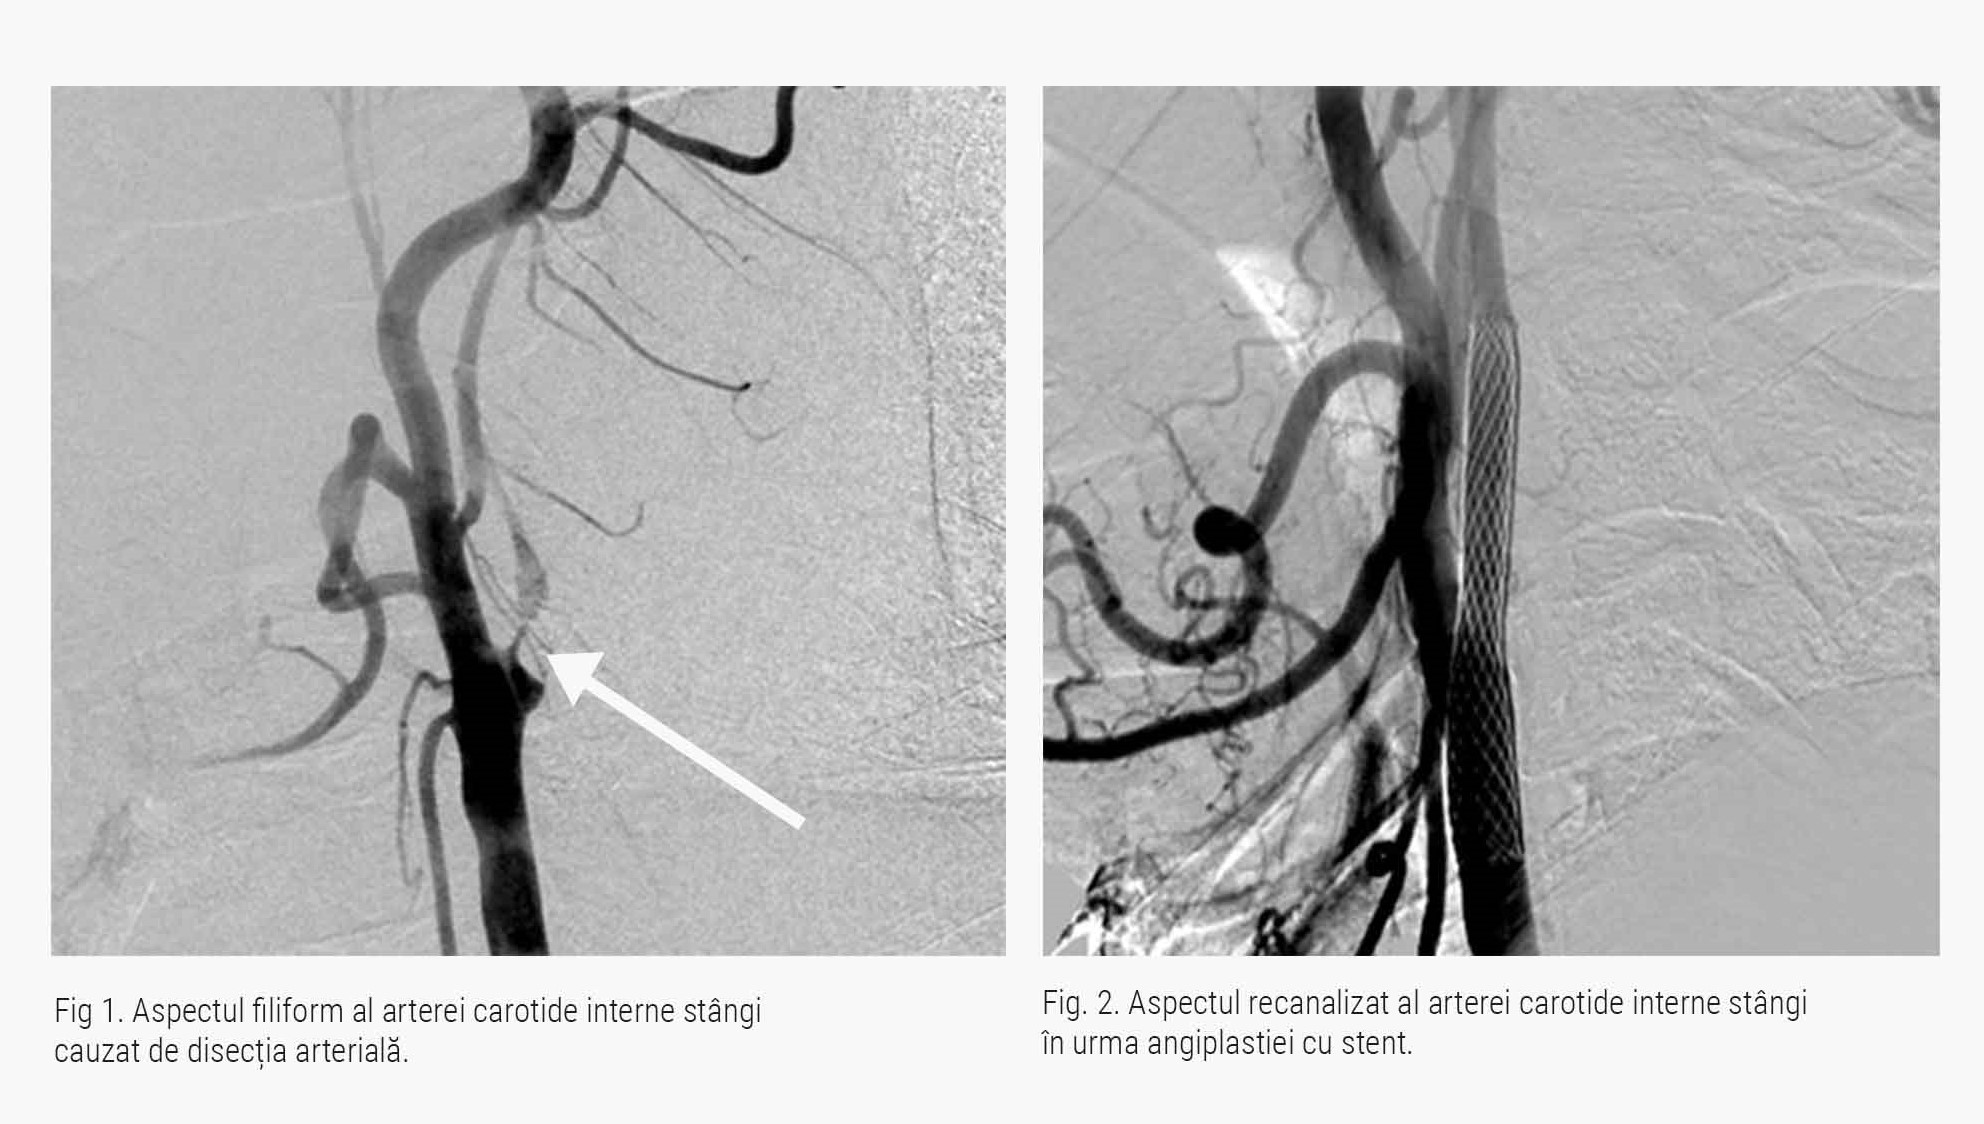

Cazul prezentat astăzi este al unui pacient în vârstă de 57 de ani, ce a suferit în urmă cu un an un accident vascular cerebral, cauzat de disecția arterei carotide interne stângi. Acesta s-a adresat echipei medicale ARES pentru efectuarea unei proceduri minim invazive, respectiv a unei angioplastii carotidiene cu stent.

Motivul pentru care a solicitat această intervenție, la recomandarea medicului curant, a fost reprezentat de recurența unor evenimente neurologice în ciuda tratamentului medicamentos maximal.

În timpul procedurii doctorul Răzvan Stănciulescu, medic radiolog intervenționist, a refăcut calibrul normal al arterei carotide interne stângi, prin inserarea unui stent la nivelul leziunii vasculare .